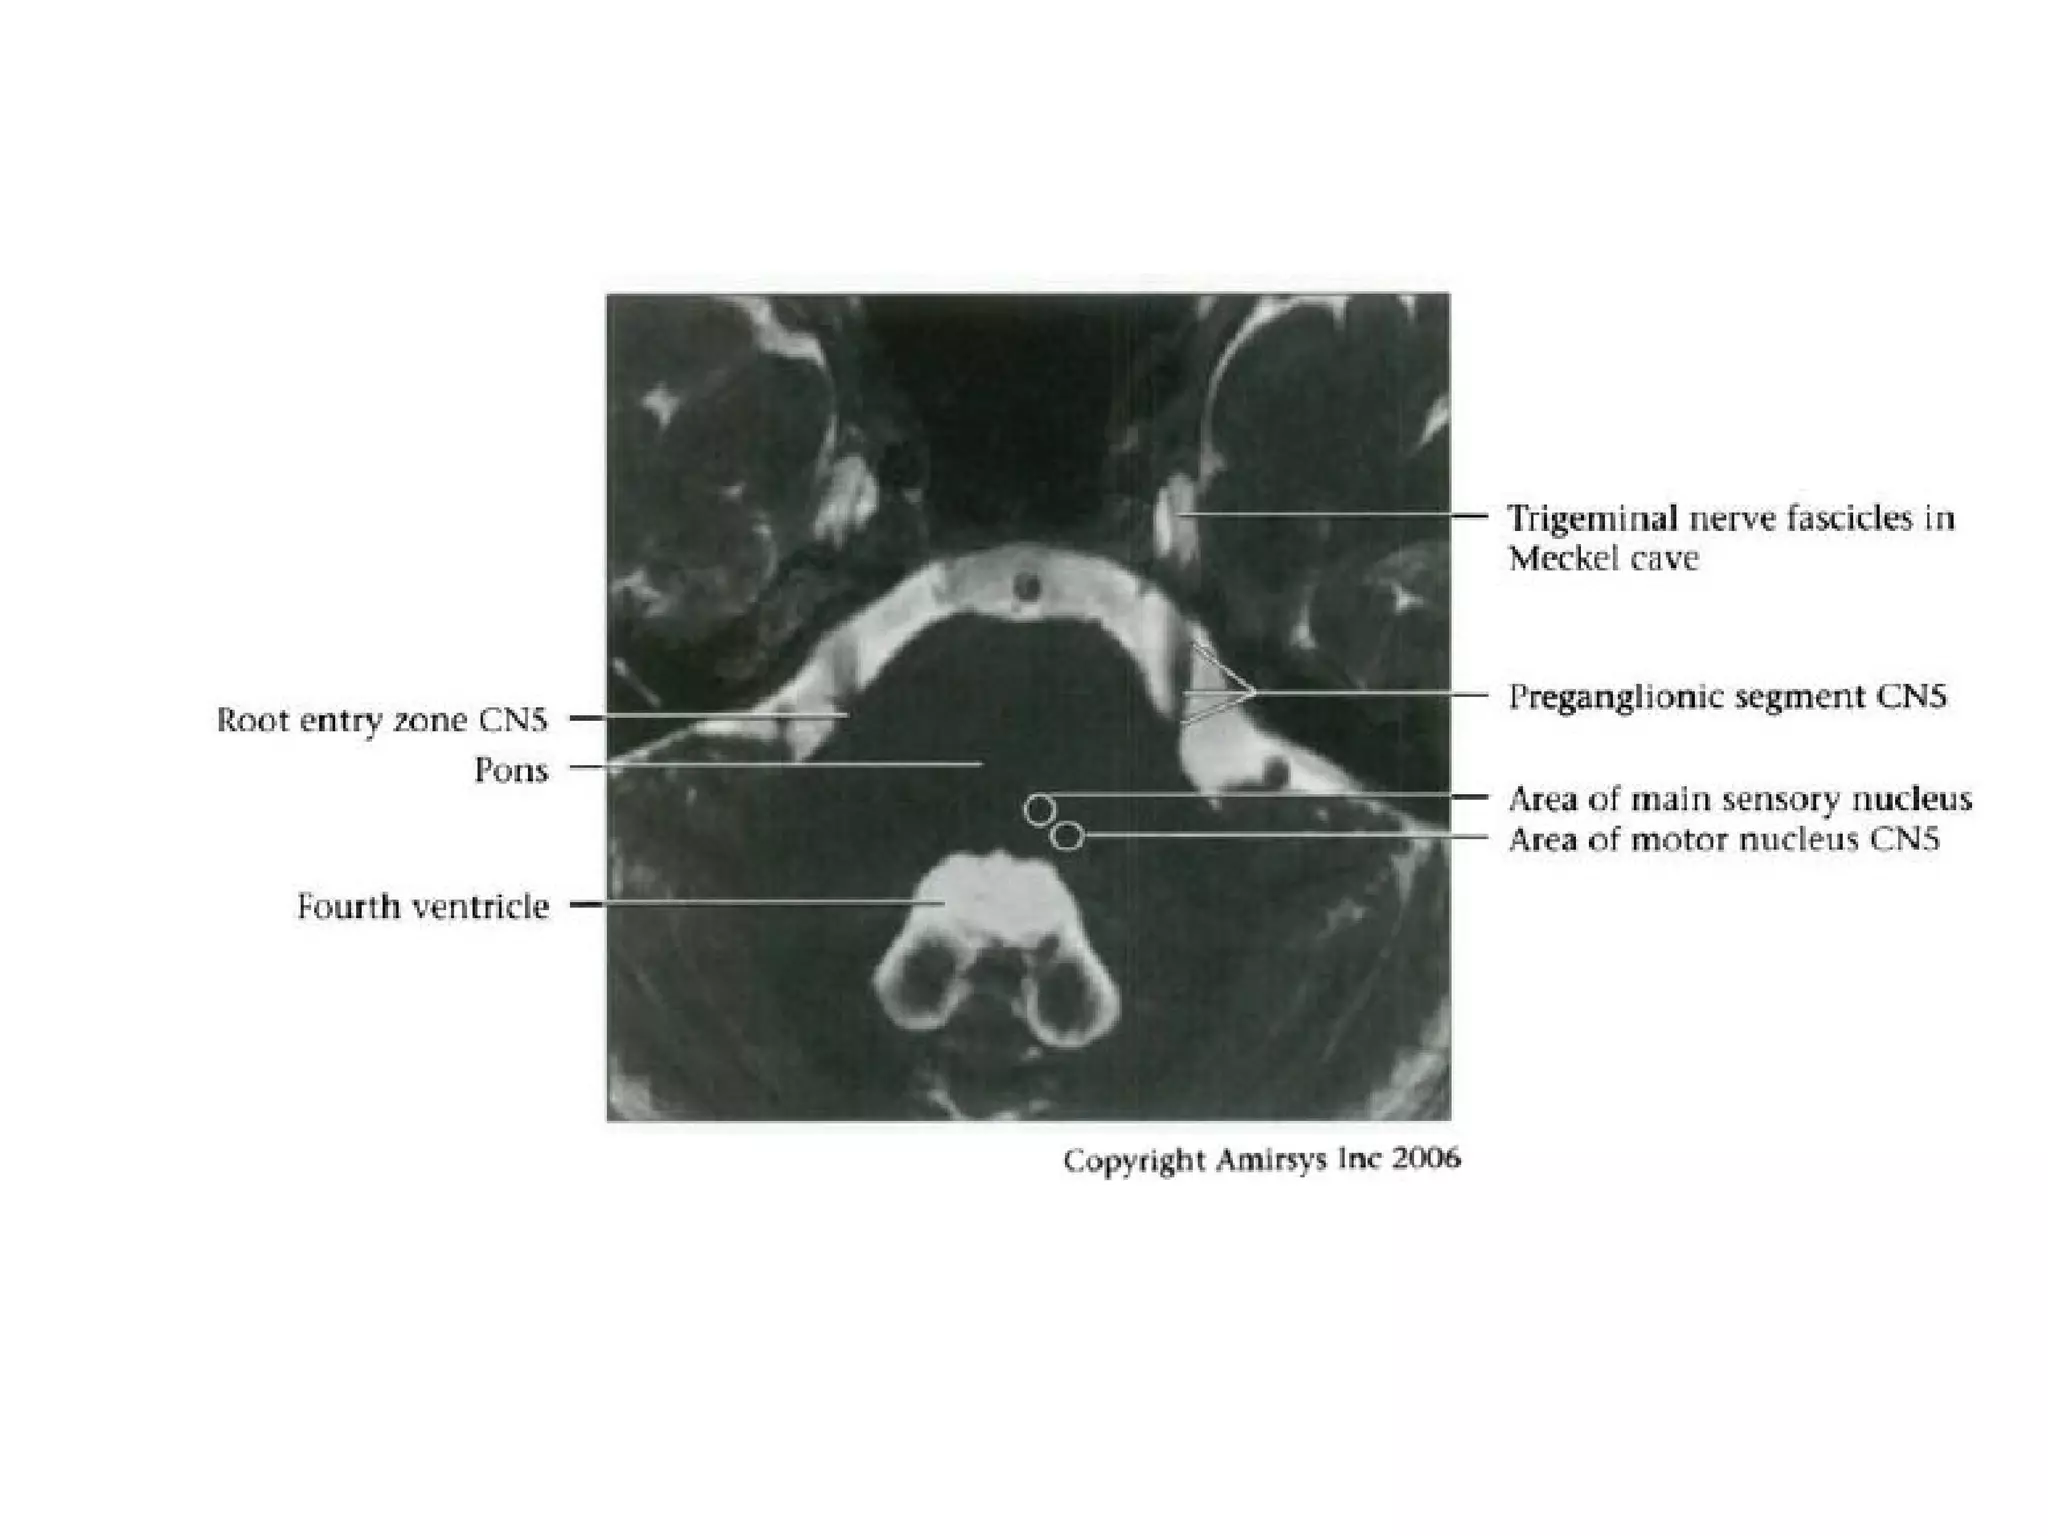

Cranial Nerve V:

The Trigeminal Nerve

• The trigeminal nerve is the largest cranial nerve.

• It is composed of a large sensory root that

runs medial to a smaller motor root.

• The roots emerge from the lateral midpons and

travel anteriorly through the prepontine cistern

and the porus trigeminus to the Meckel

(trigeminal) cave, a CSF-containing pouch in the

middle cranial fossa.

• Because the trigeminal nerve is large and its

course proceeds straight forward from the lateral

pons, it is easy to recognize on most MR

images.

RadioGraphics 2009; 29:1045–1055

• In the Meckel cave, the nerve forms a meshlike web that

can be visualized only with high-resolution imaging.

• Along the anterior aspect of the cavity, the trigeminal

nerve forms the trigeminal (gasserian) ganglion before

splitting into three subdivisions.

• The ophthalmic (V1) and maxillary (V2) divisions of the

nerve move medially into the cavernous sinus and exit

the skull through the superior orbital fissure and foramen

rotundum, respectively.

• The mandibular division (V3), which includes the motor

branches, exits the skull inferiorly through the foramen

ovale.

Trigeminal nerve.

Axial 0.8-mm-thick SSFP MR image shows the sensory

(arrowhead) and motor (large arrow) roots of the trigeminal

nerve

where they cross the prepontine cistern and enter the Meckel

cave (small arrows).